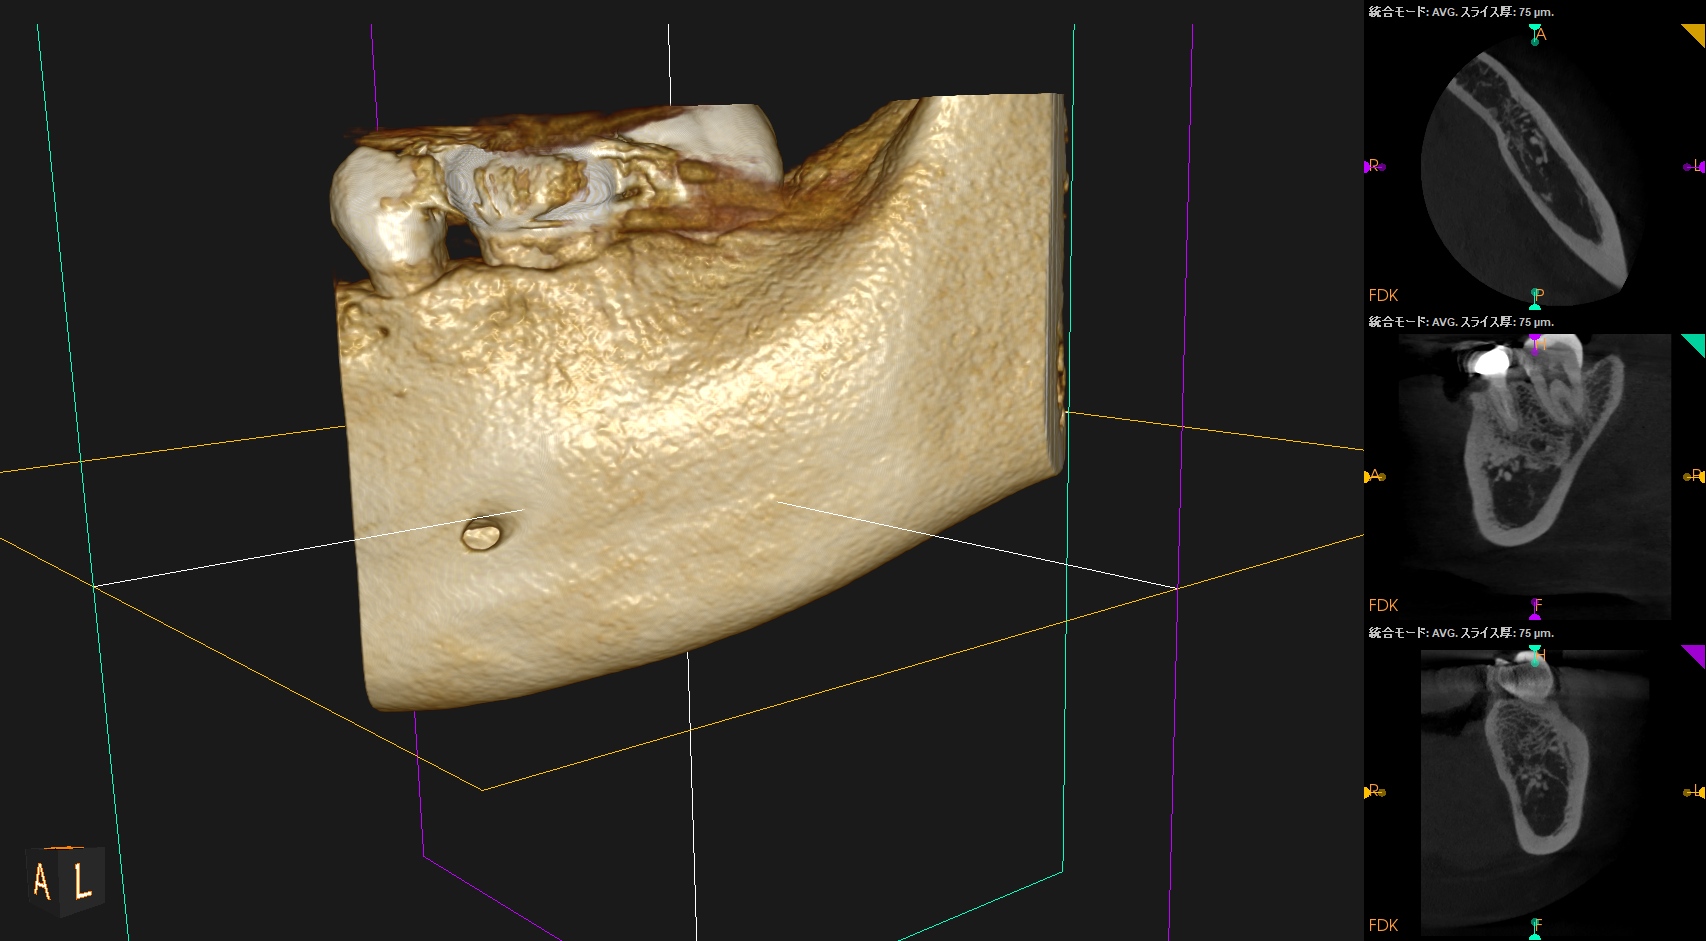

Pre-op Endo(2024.6.17)

#19 Cold N/A, Perc.(+), BT(+), Palp.(-), Perio Probe(WNL), Mobility(WNL)

臨床症状の原因は#19の近心根の根尖病変だろう。

再根管治療に見込みはないため、Apicoectomyなのだが

当該部位を2mm Osteotomyすると#19 MのApexが発見できそこを3mm切断するには頬舌径が6.2mm必要である。

Pulp Dx: Previously treated

Periapical Dx: Symptomatic apical periodontitis

Recommended Tx: M Apicoectomy

当該部位をOsteotomyした。歯槽骨は2mm削合する必要がある。

Apexを3mm削除し取り除いた。

術後にPA, CBCTを撮影した。